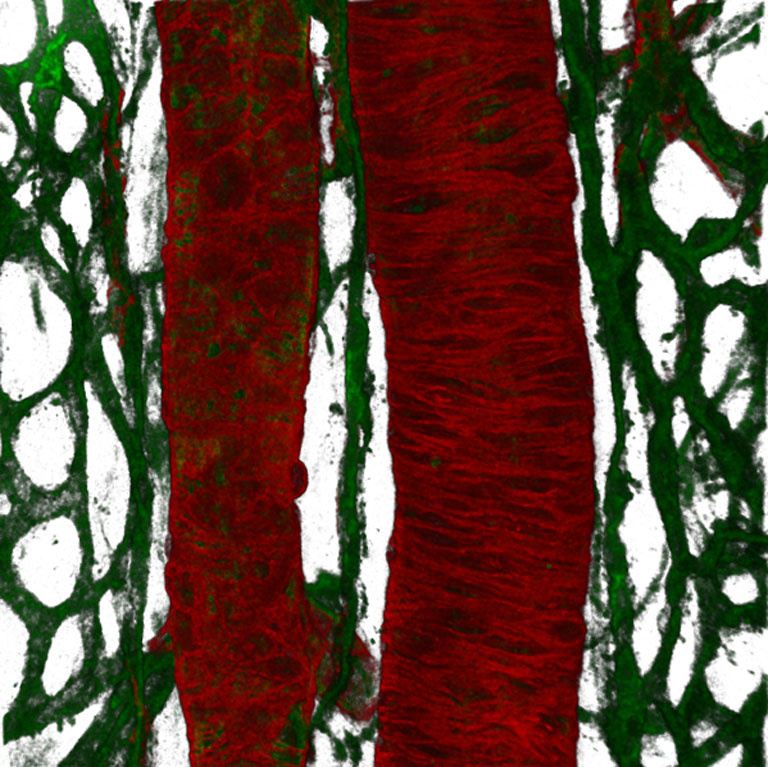

Submitted by Christopher Turner of the Hynes Lab at the Koch Institute

Confocal Micrograph

"We took this confocal image of a large artery and vein to see whether the loss of cell surface receptors called integrins affects angiogenesis - the growth of new blood vessels. Tumor angiogenesis is an important step which allows tumors to grow and metastasize. If we can stop tumor angiogenesis, we may be able to inhibit tumor growth."